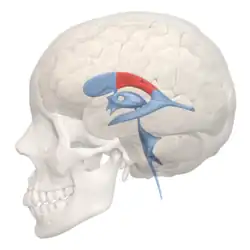

Scheme showing relations of the ventricles to the surface of the brain; oriented facing left. | |

Position of lateral ventricles (shown in red)